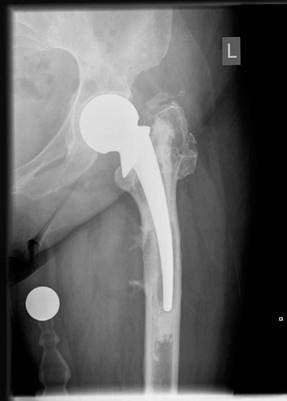

Structured Hip Oral Examination Question 2 EXAMINER : This is an anteroposterior (AP) radiograph of a 52-year…